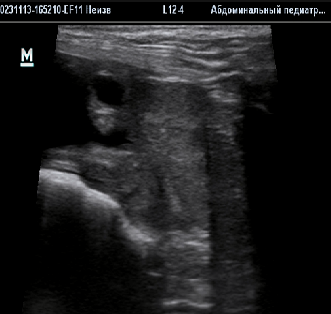

• Для определения состояния предстательной железы используется ультразвуковое исследование (рис.1);

• Под контролем УЗИ также проводится аспирационная биопсия – специальной иглой берутся образцы тканей простаты и исследуются гистологически.;

Рис.1. Увеличенная предстательная железа с единичны кистой и неровными контурами.